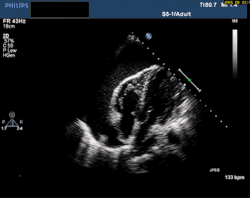

| Echocardiogram showing pericardial effusion with signs of cardiac tamponade | |

Chest radiography may reveal cardiomegaly, pneumonia, pleural effusion, and/or mediastinal widening.[4] Electrocardiogram (ECG) is a component of the diagnostic work-up which may suggest pericarditis as the underlying cause of symptoms. The ECG findings for purulent pericarditis are similar to those for other etiologies of pericarditis. ECG findings may include diffuse S-T segment elevation, diffuse T wave inversion, low QRS voltage, and/or electrical alternans.[4][6] Echocardiogram may be used to evaluate for fluid collection in the pericardial sac, and may be important in guiding therapy in patients with signs of cardiac compromise (i.e., cardiac tamponade).[3][7]

- Echocardiography (transthoracic or transesophageal) showing fluid accumulation in the pericardial sac surrounding the heart with possible evidence of cardiac tamponade